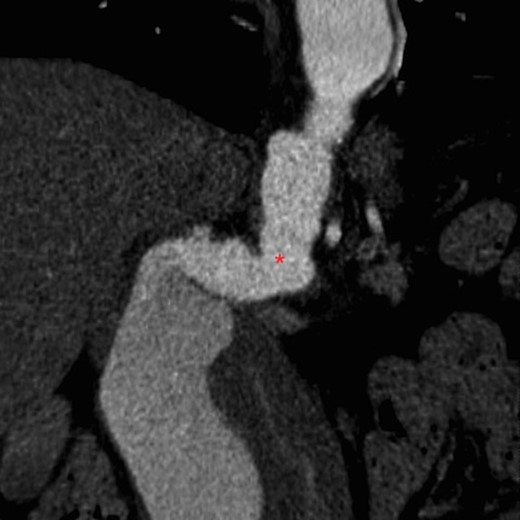

On arrival at our hospital, she was hemodynamically stable, with all vital signs within the normal range. Abdominal examination revealed a pulsating mass in the center of the abdomen. A computed tomography (CT) angiogram of aorta was performed for further evaluation that showed ectatic aorta from arch to the diaphragm. There was an 8.7-cm infra-abdominal AAA with extension into both common iliac arteries. The aneurysm neck was tortuous with an acute angle making endovascular repair challenging (Figs 1–4).

Three-dimensional construction of CT aortogram showing displaced and compressed IVC (asterisk) due to large AAA (arrow head).